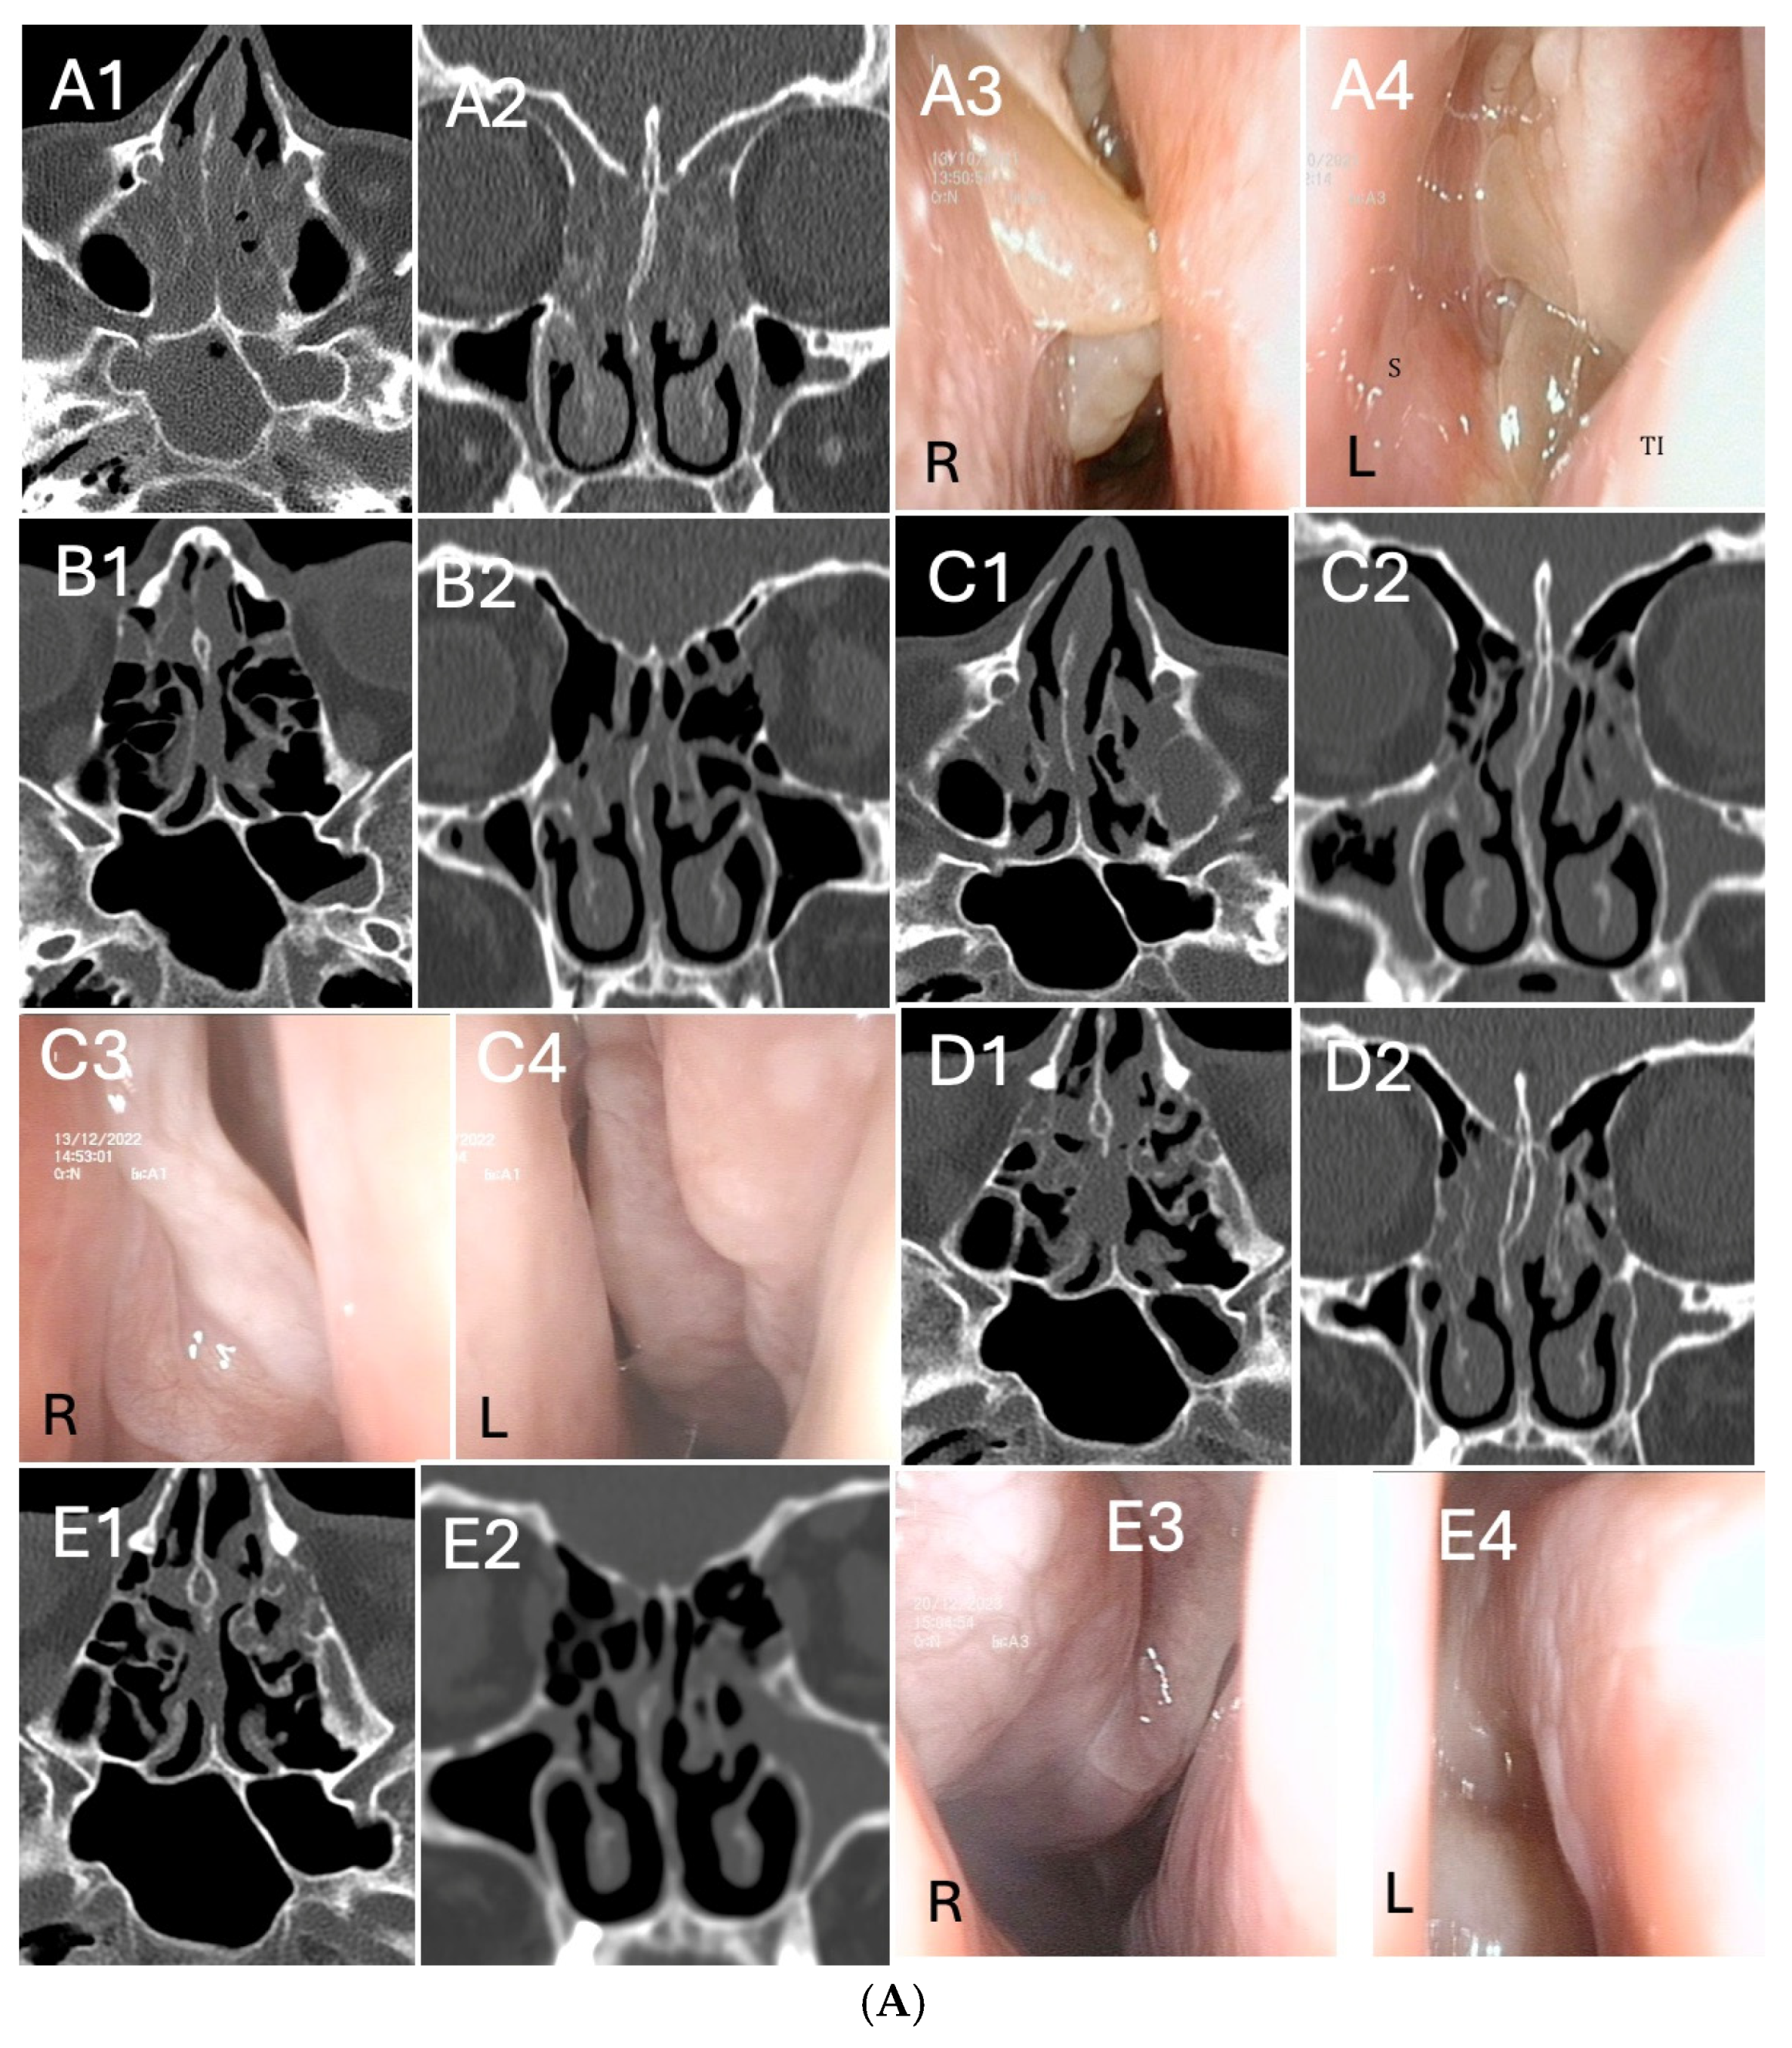

3.3. Clinical Response by Symptoms, Endoscopic, Radiologic Scores and Biomarkers Analysis During Follow-Up

3.5. Outcomes According to Previous Surgeries Stratification

3.6. Outcomes According to Asthma Diagnosis